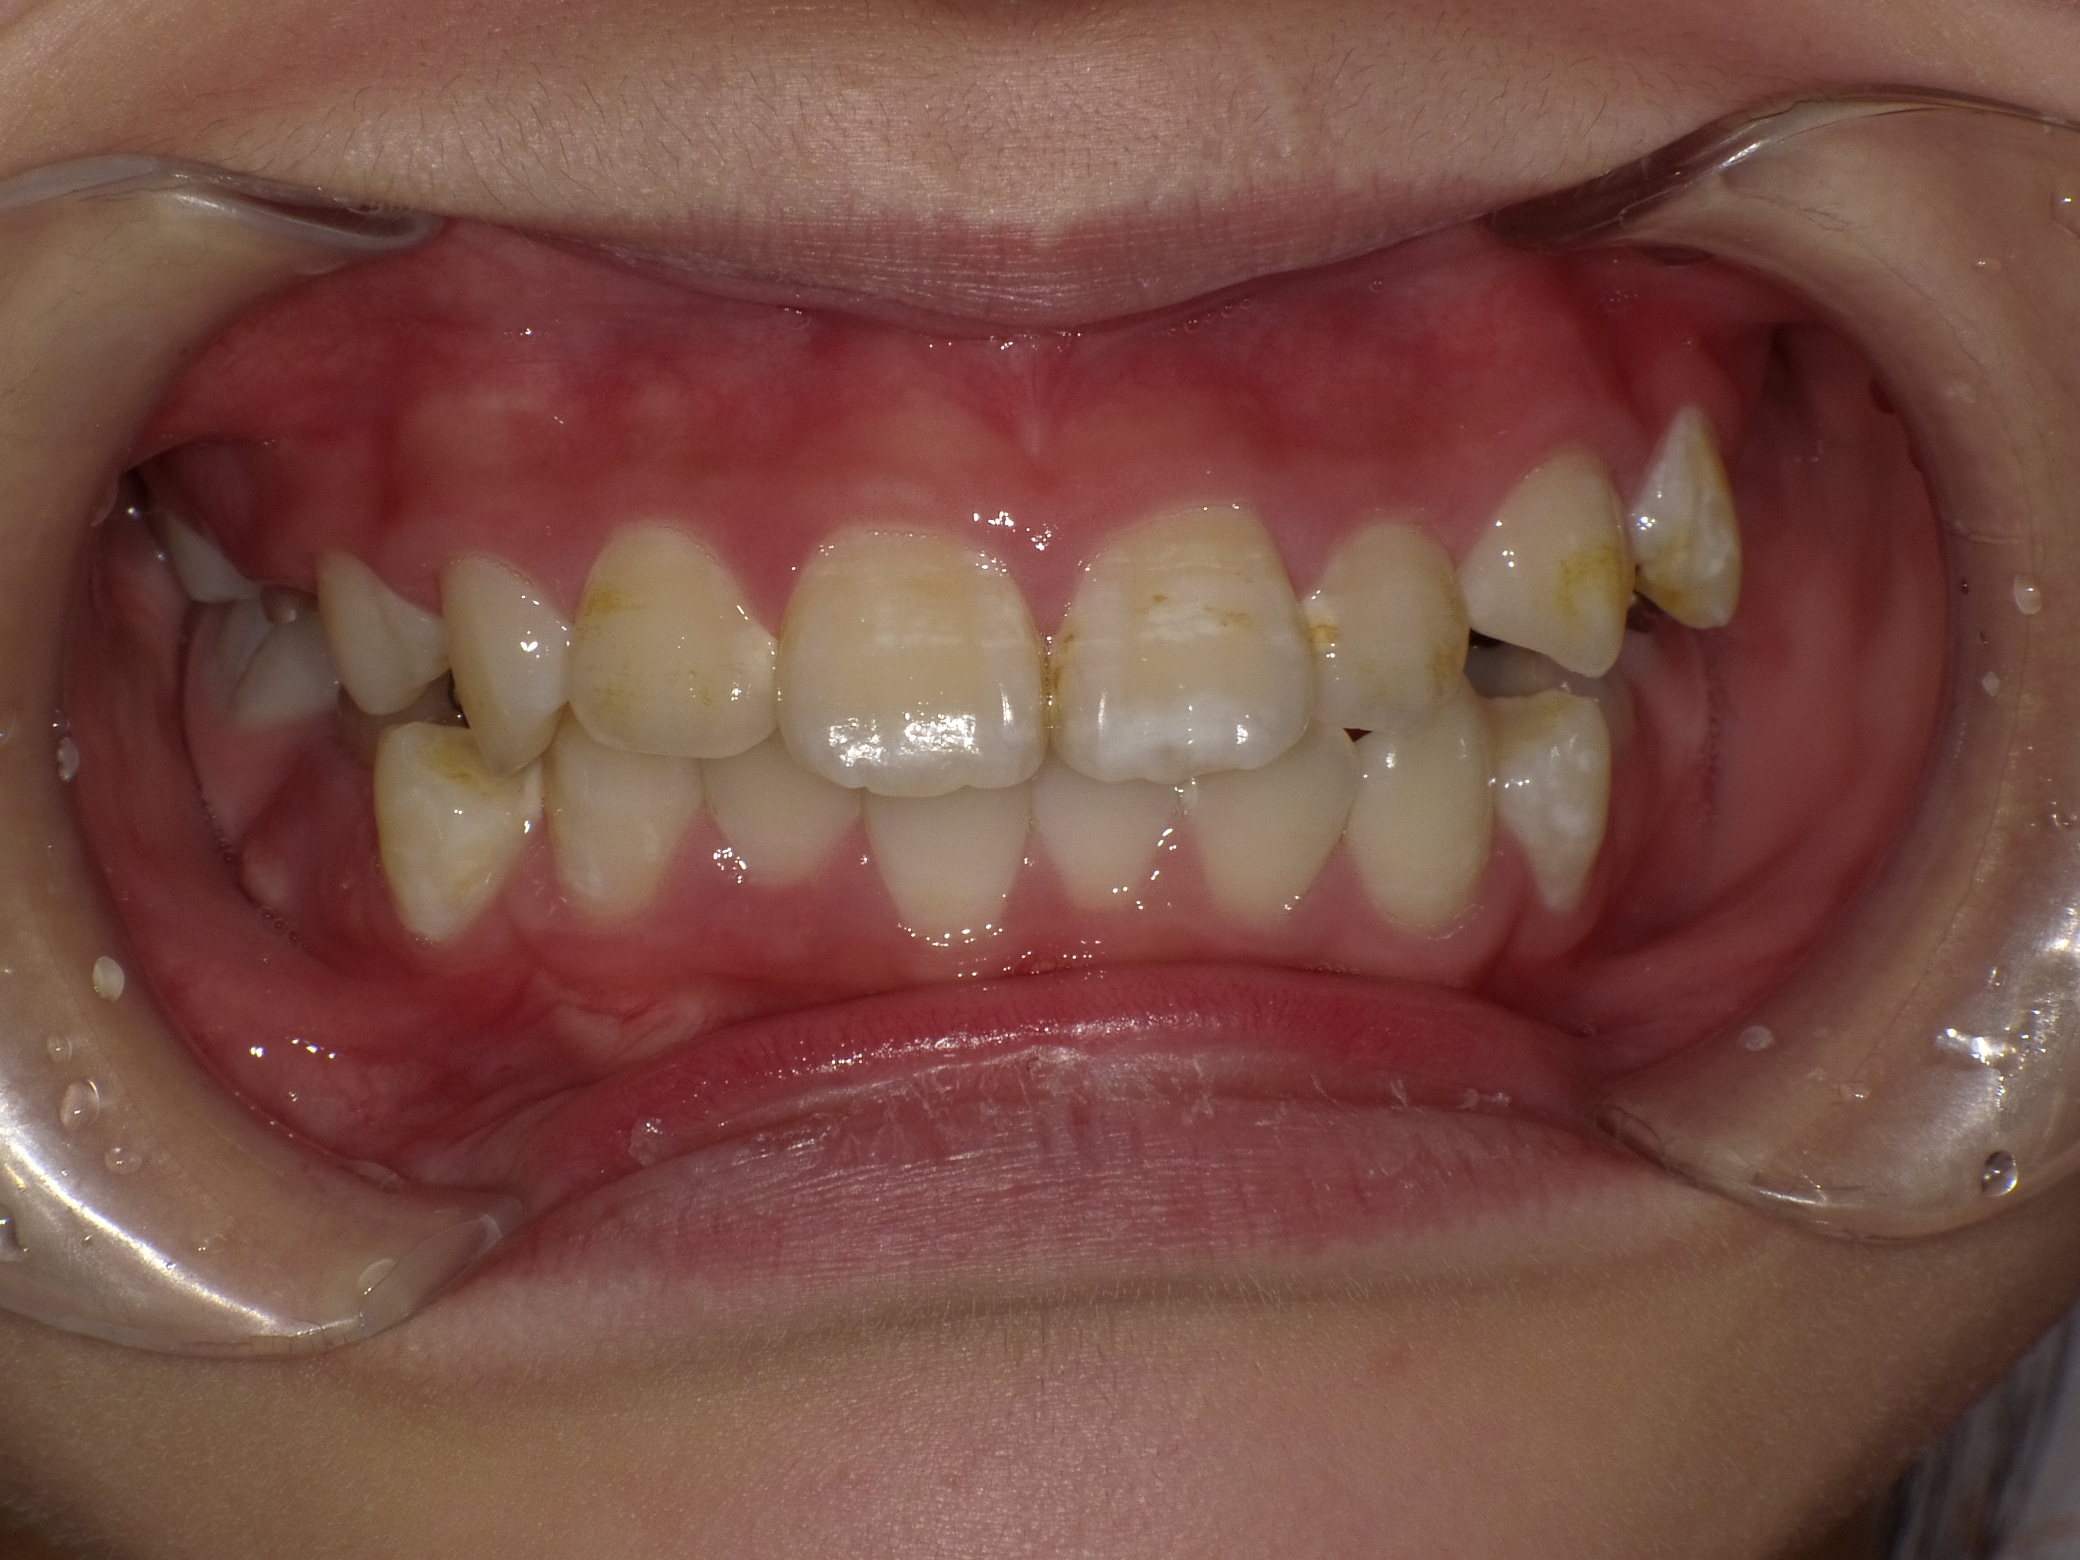

当医院ではお子様の矯正に顎の成長をサポートするような装置を使い、歯ならびを矯正します。

取り外し出来る装置のため、お子様の負担も少なく、気軽に使用できます。

当医院では歯並びだけでなく咬み合わせの確認も行っていきます。

適応年齢は小学生~中学生ですが、それ以前の年齢のお子様も定期健診で様子を診ていきますのでお気軽にご相談下さい。